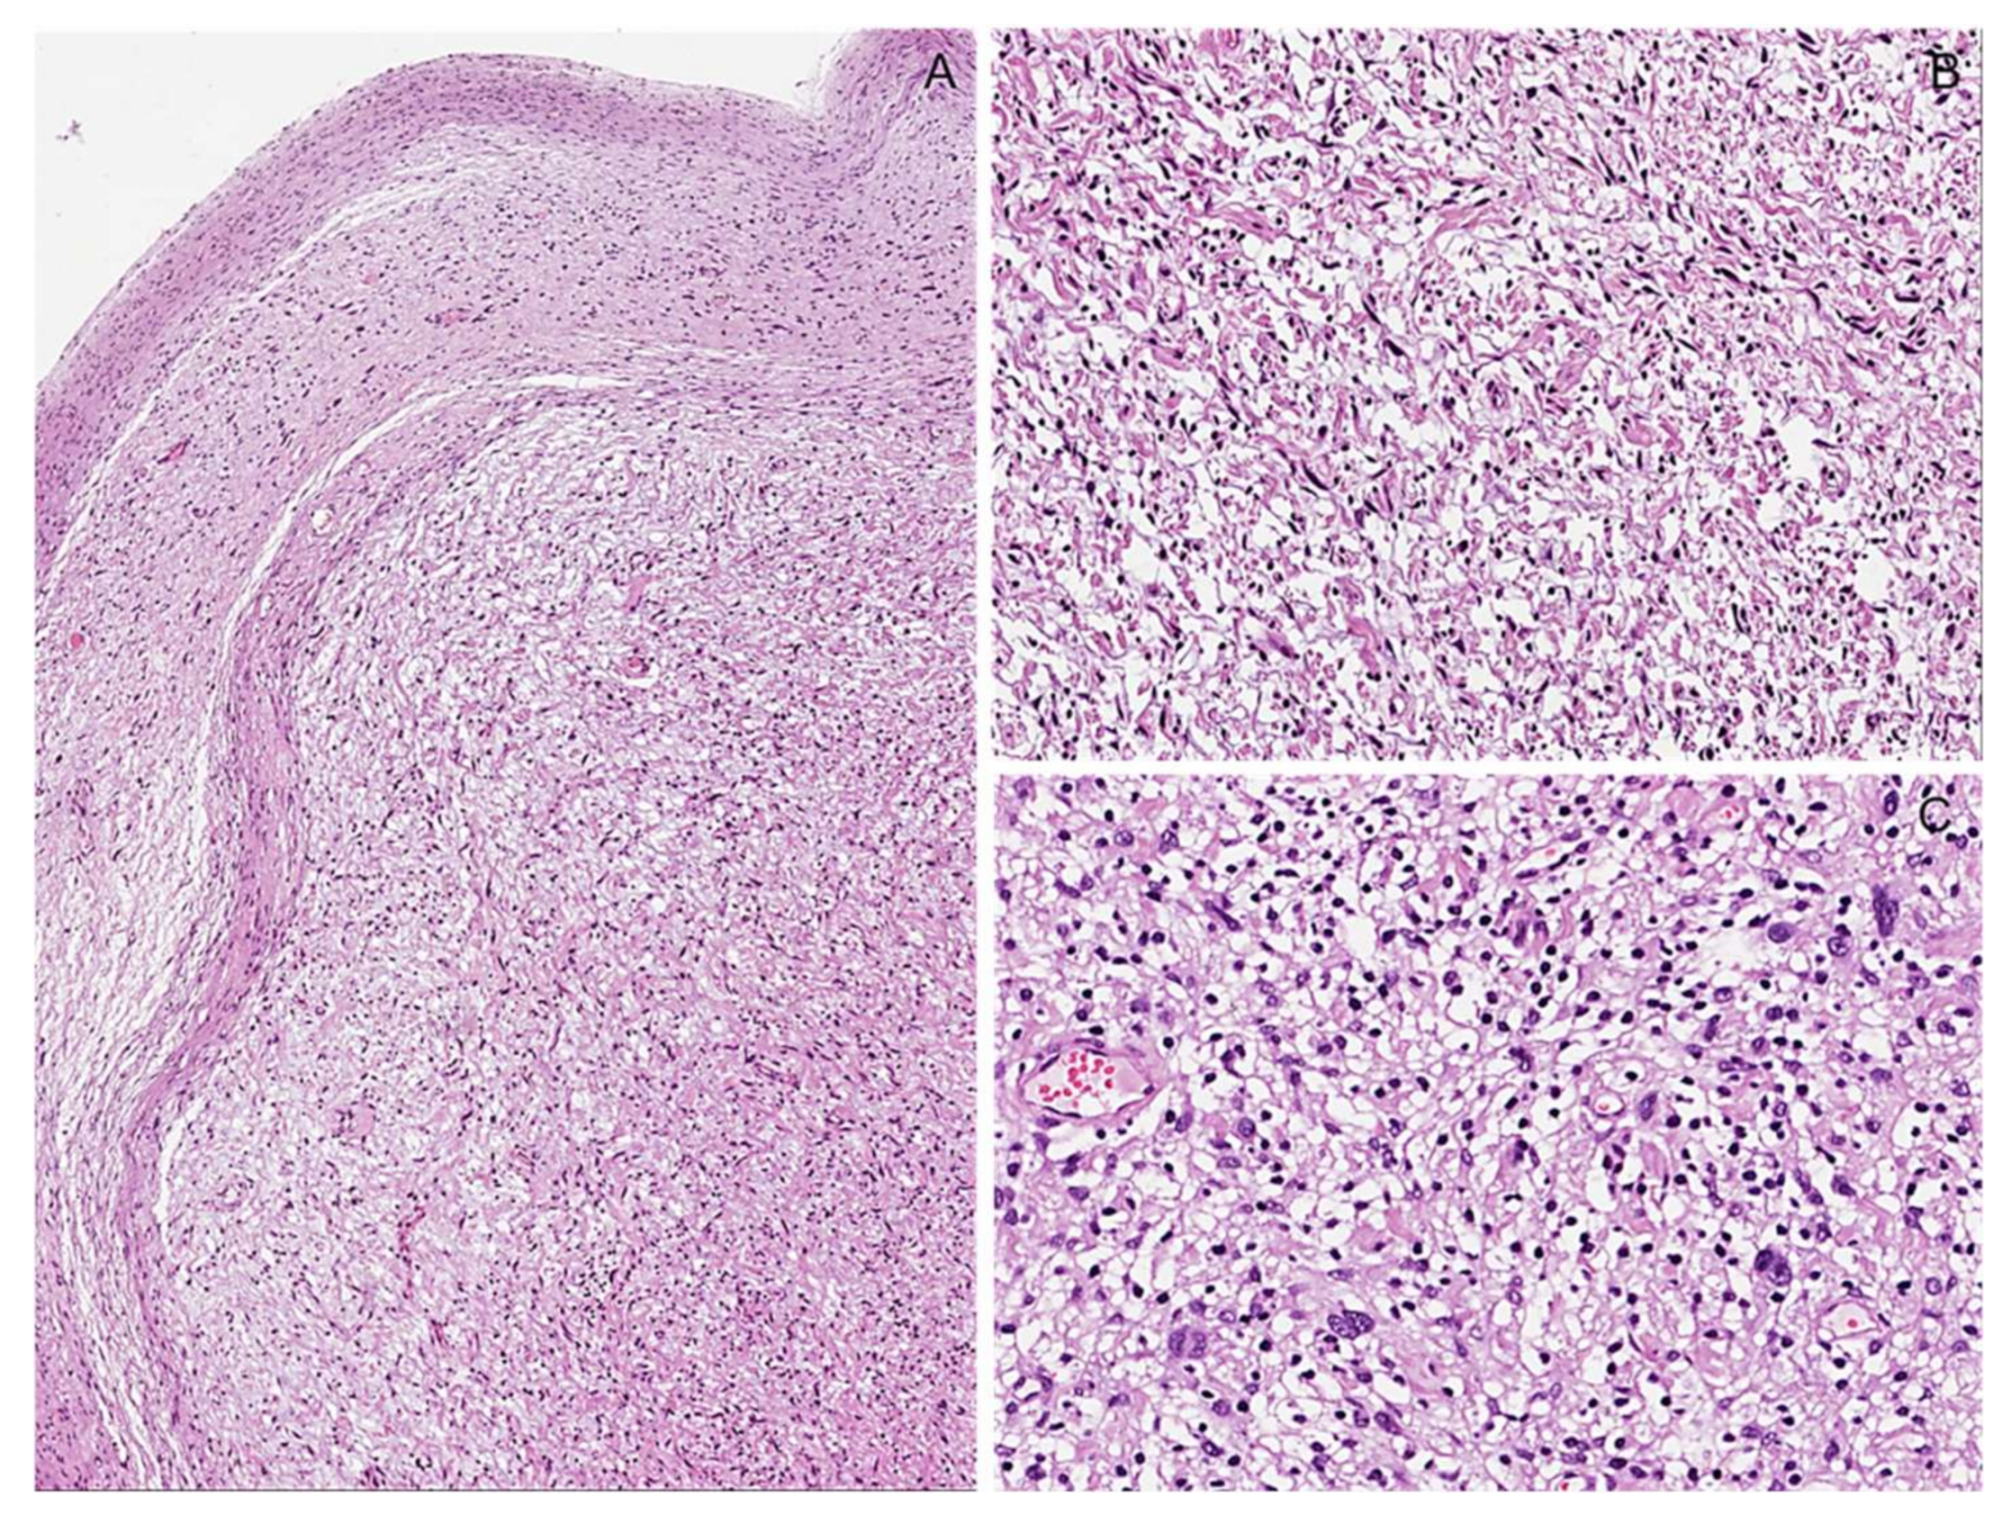

3.4. Potential Morphological Pitfalls of Malignancy in Neurofibromas: Cytological Atypia and Hypercellularity

Immunohistochemical Features